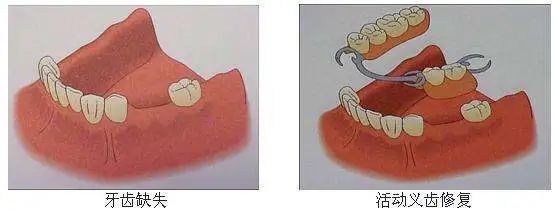

01 -可摘局部义齿

也称为活动假牙,是患者可以自由摘戴的一种修复体,主要由人工牙和其它部件组成。前者用于恢复缺失牙的形态和功能,有人工树脂牙、瓷牙等材料可供选择。

其它部件则用来适当的恢复周围软组织的形态,并对整个义齿起到固位和支持的作用。一般在拔牙后1-2个月即可开始取模,取模后1-2周则可戴牙。

「适应症」:从单颗牙到多颗牙缺失,均可适用;作为后面两种修复方式的一个过渡;青少年缺牙需要维持缺牙间隙者;不愿意磨除旁边健康牙又不能耐受种植手术者。

向左滑动查看活动义齿修复,慎滑(图片来源于必应)

「优点」:适应症广,磨除牙体组织少,便于清洁,制作相对简便,费用相对较低,便于修理。

「缺点」:体积大、部件多、初戴时有异物感,可能影响发音;稳定性和咀嚼效率相对较低;若口腔卫生差,容易出现黏膜溃疡;设计不合理时易损伤旁边健康牙。